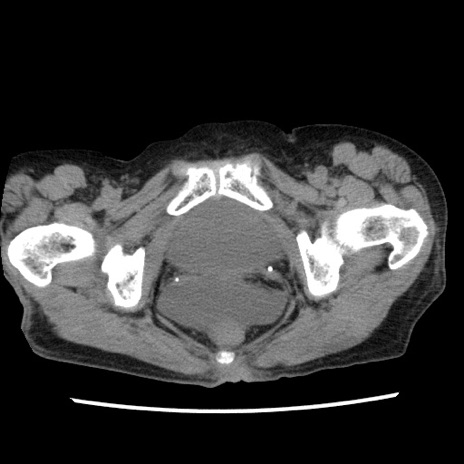

冠状断像

【症例】80歳代女性

【主訴】腹痛

【現病歴】8時間前から腹痛あり来院。

【既往歴】糖尿病、脂質異常症、子宮体癌にて子宮全摘術

【身体所見】意識清明・会話良好だが腹痛で苦悶様、全腹部にわたって反跳痛と圧痛あり

【データ】WBC 13600、CRP 0.14、LDH 224、CK 90